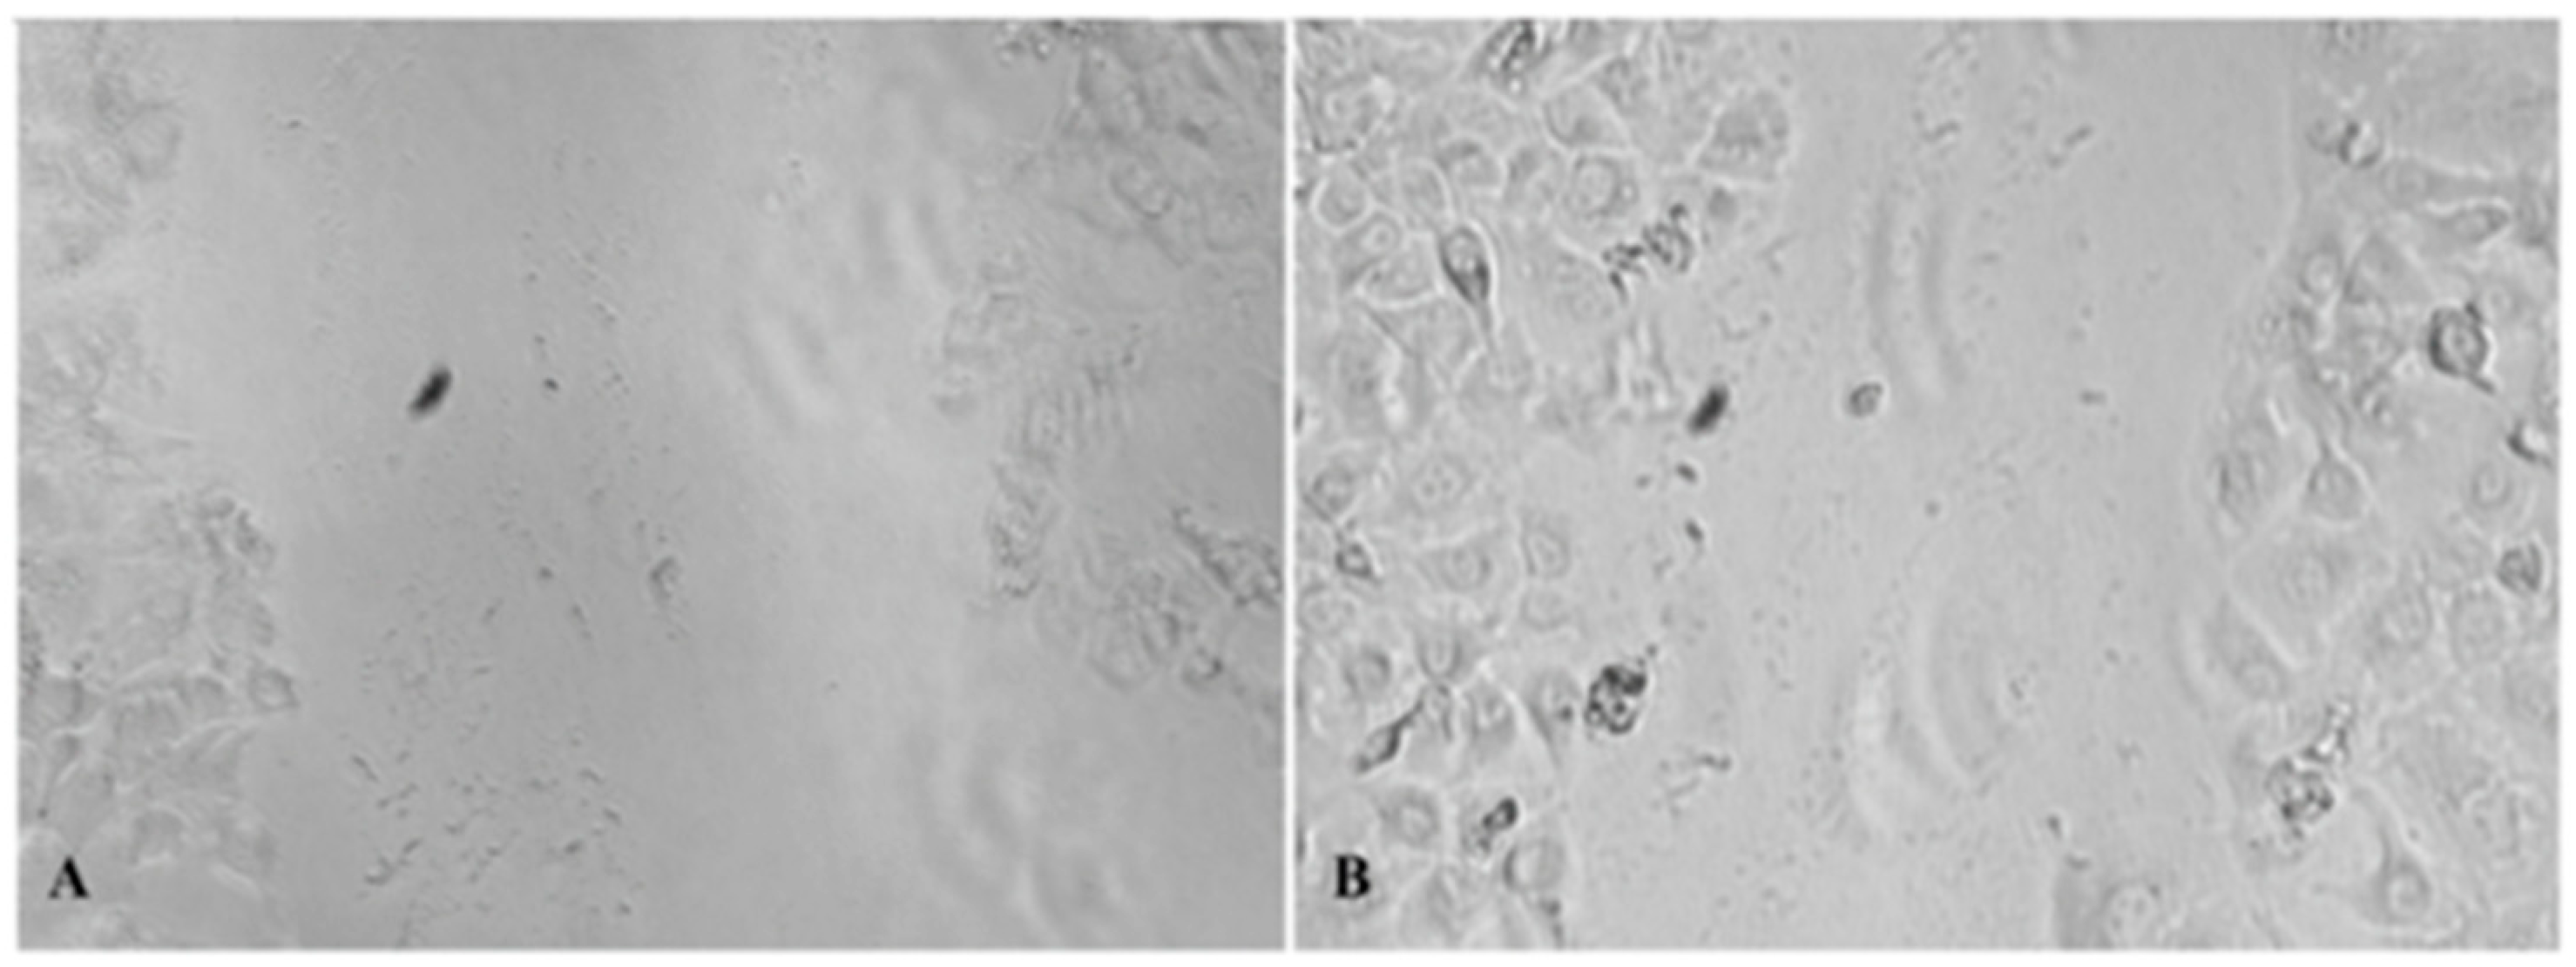

4.6. In Vitro Wound Healing Assay